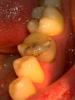

Наконец решил заняться зубами, т.к. стоматологов побаиваюсь, обращался редко. Сейчас мне 28 лет, три мертрых 6-ки, нервы были удалены более 6-8 лет назад. Хочу не спеша и спокойно привести зубы в хорошее состояние, чтобы они мне прослужили максимально долго, чтобы я все-таки не потерял их и в старости не думал про имплантацию. Конкретно сейчас интересует нижняя левая шестерка, вот она:

Изначально поводом послужило то, что пломба отходит спереди, и туда попадает пища, и в зубе, под пломбой, скорей всего, уже образовался серьезный очаг кариеса. Думал поставить пломбу, но специалсты говорят, что уже надо коронку. Какие вы посоветуете варианты? Эстетически мне все-равно, как он будет выглядеть. Главное, подчеркиваю - надежность, долговечность.

Перелечить-и вкладки, коронки. Седьмые нижние тоже требуют внимания: кариес. На 26 пломбу нужно менять. На 27, скорее всего, кариес на передней контактной пов-ти.